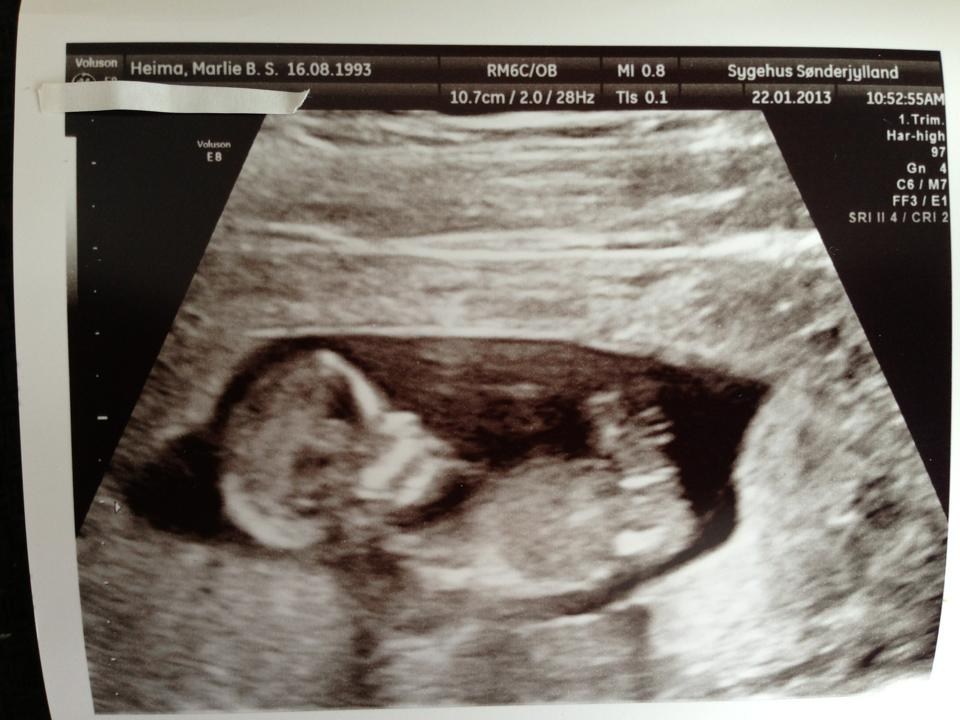

Så blev NF scanningen overstået i dag. Barnet var et "pragt eksemplar" som damen sagde og alt var helt som det skulle være + en lav risiko for Down Syndrom

Vi fik hørt hjertelyd hvilket var helt igennem fantastisk og vi fik også set den bevæge sig rundt derinde - super dejligt <3

Lige et billede